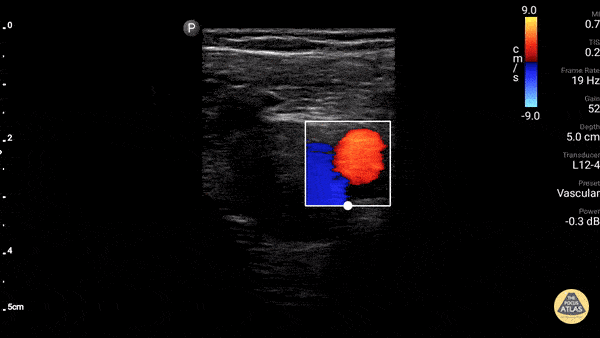

Vascular - Great Saphenous Vein

The greater saphenous vein, as it takes off from the femoral vein. Make sure to scan up this high and start compressions here to rule out DVT in the lower extremity. Dr. Gordon Johnson